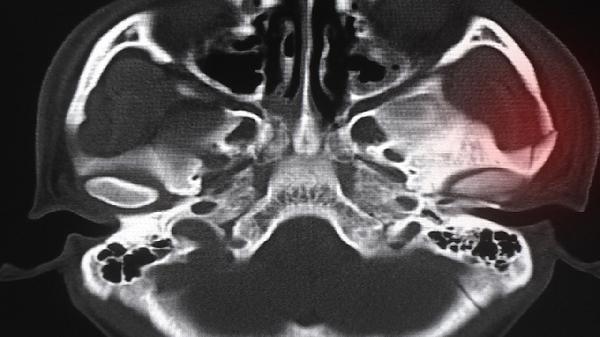

双侧上下颌骨多发占位是什么意思

双侧上下颌骨多发占位通常指影像学检查中发现颌骨内存在多个异常组织团块,可能由颌骨囊肿、骨纤维异常增殖症、成釉细胞瘤或转移性肿瘤等疾病引起。